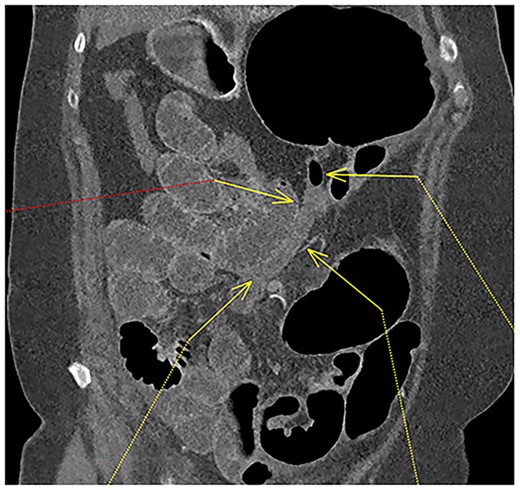

A 61-year-old female with known Marfan Syndrome was admitted to the emergency department with 3-day history of abdominal pain, nausea, vomiting and bowels not opening. Past medical history included three previous episodes of Type A aortic dissection, recent aortic root and ascending aorta replacement alongside bioprosthetic aortic valve replacement. She was an ex-smoker and usually independent at home. On presentation, the patient was haemodynamically stable and apyrexial. Biochemical results were unremarkable except for a Lactate dehydrogenase (LDH) of 309 and a C-reactive protein (CRP) of 101. On examination, she had a diffusely tender and distended abdomen, without signs of peritonism. An erect chest X-ray shows left pleural effusion with a dilated aortic root (Fig. 1). A computed tomography (CT) of thorax, abdomen and pelvis was requested, which demonstrated a caecal volvulus with a dilated cecum of 8.8 cm and upstream small bowel dilatation with air fluid levels, and a chronic aortic dissection extending from the ascending thoracic aorta to the common iliac (Figs 2–4). Following consultation between radiologists, cardiothoracic surgeons and general surgeons, she underwent an emergency laparotomy and right hemicolectomy with side-to-side ileocolic anastomosis. Intraoperatively, the caecal volvulus, comprising a dilated ascending colon measuring up to 10 cm, was delivered and resected along with its mesentery. The patient was admitted to the intensive care unit post-operatively for close blood pressure monitoring and control and stepped down to level 3 wards on day-2 post-operation. Her operation was complicated by a small infected wound haematoma thatwas managed with a 5-day course of ciprofloxacin. A CT of the abdomen and pelvis to investigate a rising CRP on day-9 revealed a subcapsular liver haematoma thath was managed conservatively. The patient was discharged 12-days post-operatively. Histology from the resected colon showed evidence of ischaemia in keeping with a closed loop obstruction such as caecal volvulus. There was also an incidental T1 N0 colonic tumour arising from a sessile serrated polyp and two other serrated polyps. A colonoscopy to inspect the remaining colon has been arranged.

CT thorax, abdomen and pelvis coronal view demonstrating a distended, twisted caecum, caecum in the left upper quadrant, small bowel distension (red arrow) and a decompressed ascending colon (green arrow).

Fluid-filled mid to distal appendix with some gas in the proximal part outlined with yellow arrows. Appendix is seen within the upper abdomen, indicating an increased likelihood of caecal volvulus.